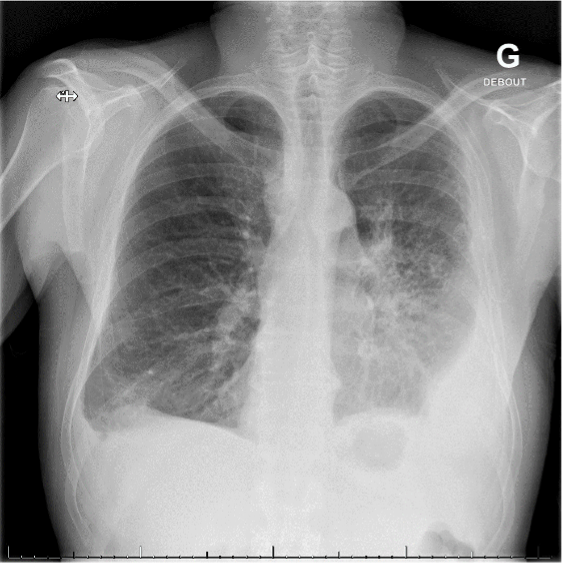

Un patient de 60 ans consulte les urgences pour une dyspnée en péjoration depuis 1 semaine associée à une toux et une douleur thoracique.

L’examen clinique et le bilan paraclinique mettent en évidence une pneumonie à Escherichia coli. L’ECG effectué dans ce contexte montre des signes de péricardite. Au vu de l’élévation des troponines, un diagnostic de myopéricardite est retenu.

Au laboratoire, on retrouve le plus souvent une augmentation des paramètres inflammatoires et des troponines. Selon l’étiologie, d’autres valeurs peuvent être perturbées. Les modifications typiques de l’ECG sont une surélévation diffuse du segment ST et un PR descendant. La radiographie du thorax peut montrer un élargissement de la silhouette cardiaque faisant suspecter un épanchement, ou aider dans la recherche de l'étiologie. L’échocardiographie permet de rechercher un épanchement péricardique et de visualiser les répercussions au niveau de la fonction cardiaque. En cas de douleur thoracique rétrosternale, la priorité est d'exclure une coronaropathie par coro-scanner ou coronarographie.

Image proposée par l'Hôpital Riviera-Chablais.